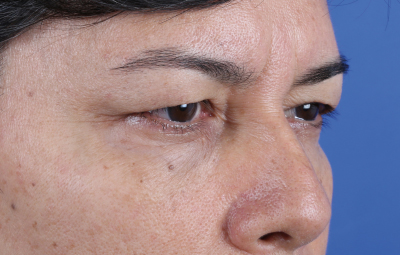

Es una ayuda diagnóstica complementaria que se utiliza para capturar imágenes de cualquier parte del cuerpo, aplicando técnicas que permitan obtener fotografías proporcionales, detalladas y nítidas; empleadas para medir, trazar, predeterminar y planear un proceso quirúrgico.

Es utilizada para crear imágenes del cuerpo humano, o partes de él, con propósitos clínicos que buscan revelar, diagnosticar y planear un tratamiento médico.